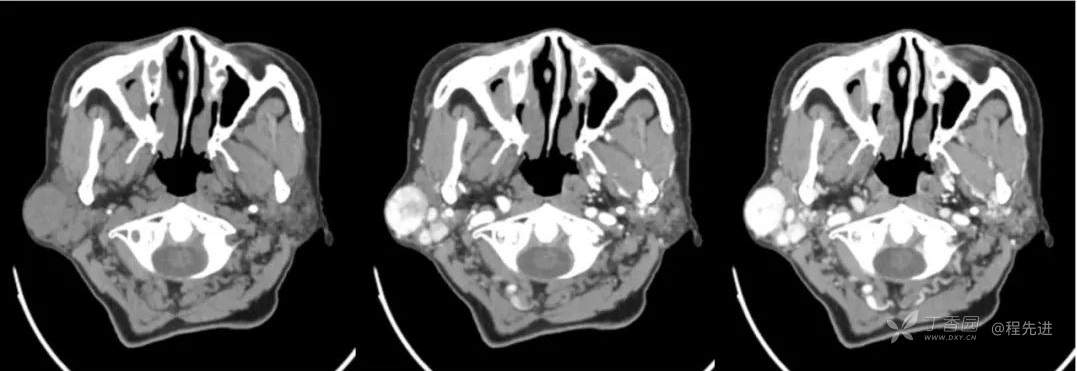

红五月特别精彩病例|发现右侧耳下肿物12年,罕见典型病例,见过就可以秒【病理公布】

简要病史:发现右侧耳下肿物12年,不痛,缓慢生长

既往史:19年前因右侧腮腺肿物在当地医院行手术(具体不详),17年前因右侧腮腺肿物复发再次在当地医院手术(具体不详)

体格检查:右侧耳下可扪及大小约3*3cm肿物,质地中,边界清,活动可,无明显压痛。颈部未扪及明显肿大淋巴结